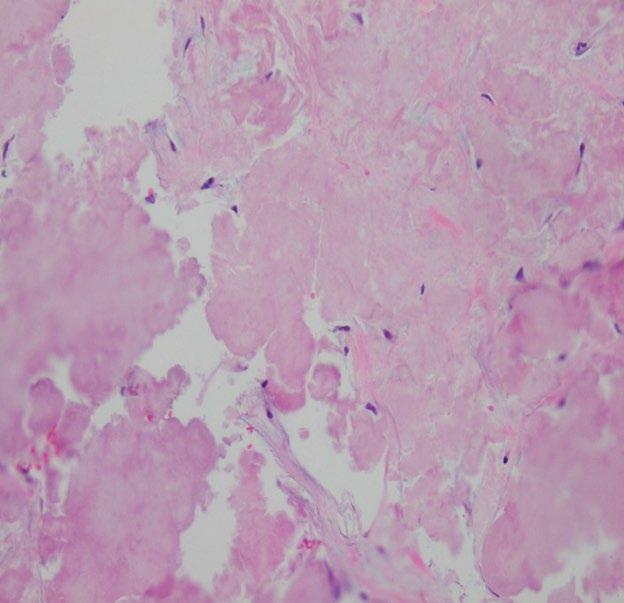

Create a flipbook